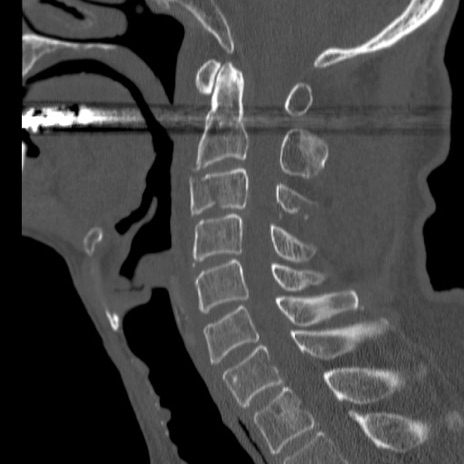

症例46 頚椎CT(矢状断像)

【症例】80歳代男性

【主訴】両側頚部〜上肢のしびれ

【現病歴】昨日、自宅内で転倒、その後より上記症状あり。意識障害なし。

【身体所見】両側上肢のallodynia(熱痛覚過敏)あり。MMTおよびDTRは正確な所見取れず。両上肢の挙上はなんとか可能。

異常所見と診断は?